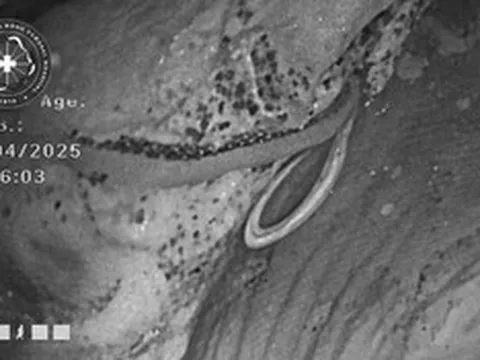

Ê-kip thực hiện ca phẫu thuật.

Ngay sau đó, gần 200 cán bộ y tế từ nhiều chuyên khoa lâm sàng và cận lâm sàng đã làm việc xuyên đêm với tinh thần khẩn trương và độ chính xác tuyệt đối.